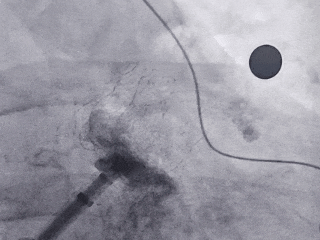

术中DSA左心耳造影

肝位左心耳造影

右肩位左心耳造影

-

心耳呈反鸡翅,穿刺位置偏下偏前

术中DSA左心耳造影测量

肝位左心耳测量,开口30.8mm,上叶深度28mm,

为大开口反鸡翅型左心耳

穿刺高低位置合适,靠下靠前